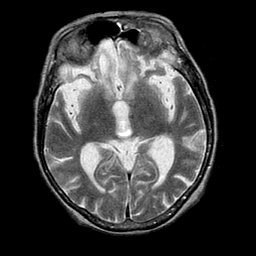

Pick's Disease, MR Study mr-t2 -- Slice #10

[Home][Help][Clinical] Slice 10